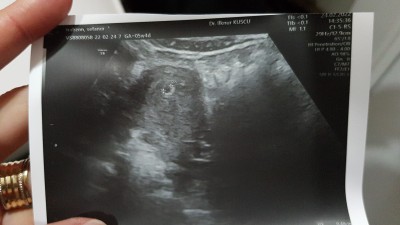

Beta 1776 dan 2 gün sonra 1912 ye çıktı kürtaj dediler çıktım yaptırmadım. Özelde bi doktora gittim kese gözüktü .P tesi günü gel bebek oluşmuşmu bakalım dediler böyle birşeyle karşılaşan var mı

Gebelik haftası 5

Bugün doktora gittik bebeği gördük ve kalbini duyduk çok şükür